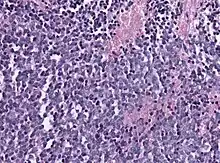

Biopsy is required for diagnosis. Pineoblastomas appear as high grade, highly cellular, small blue cells histologically. Features of aggressive malignancies can be seen, like high nucleus-to-cytoplasm ration, poorly differentiated cells, high mitotic activity, and necrosis.[13][3] Homer Wright, or neuroblastic, and Flexner-Wintersteiner, or retinoblastic, rosettes can also be seen. In contrast to other masses of the pineal gland, pineocytomatous rosettes are not present.[13] Immunohistochemistry staining will reveal neuronal, glial, and photoreceptor marker positivity. This includes synaptophysin, neurofilament protein, and CRX, a specific pineal or retinal marker, positive staining.[13][7]